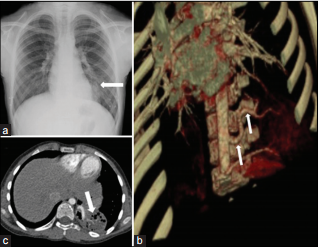

3. Secuestro pulmonar

1. Segmento del parenquima pulmonar con irrigacion pulmonar

1. No comunicado con el arbol traqueobronquial

2. Clsificacion

1. Intralobar

1. comparte el revestimiento pleural visceral

1. Diagnosticado en la infancia tardia

1. Hllazgo

1. Segmento basal posterior de un lobulo inferior

2. Puede acompañarse de

1. Cavitaciones

1. Bronquiectasias focales

1. Multiples areas quisticas

2. Extralobar

1. Separadp del tejido pulmonar

1. Dx tempranamente en la infancia

1. Hllazgos

1. Masas retrocardiacas en angulo cardiofrenico

1. Bien definido